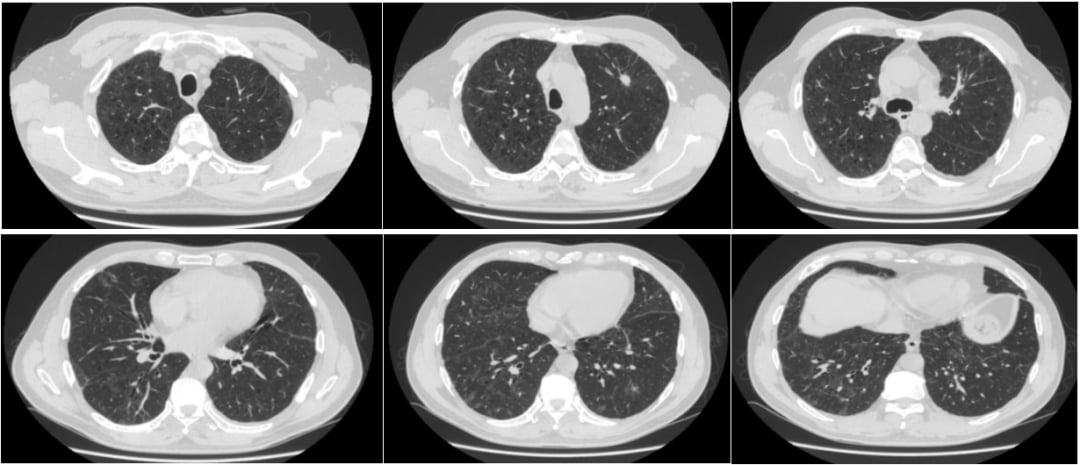

2025年9月,患者开始口服阿美替尼(Aumolertinib),同时辅以口服泼尼松(Prednisone)进行预防性管理,并逐渐减量停药。仅仅服药一个月后复查CT,令人欣喜的结果出现了:双肺的间质性肺炎病灶较前明显吸收!患者的病情持续稳定,截至目前已连续服用阿美替尼5个月,且实现了长达8个月的无病情进展(PFS),生活质量良好。